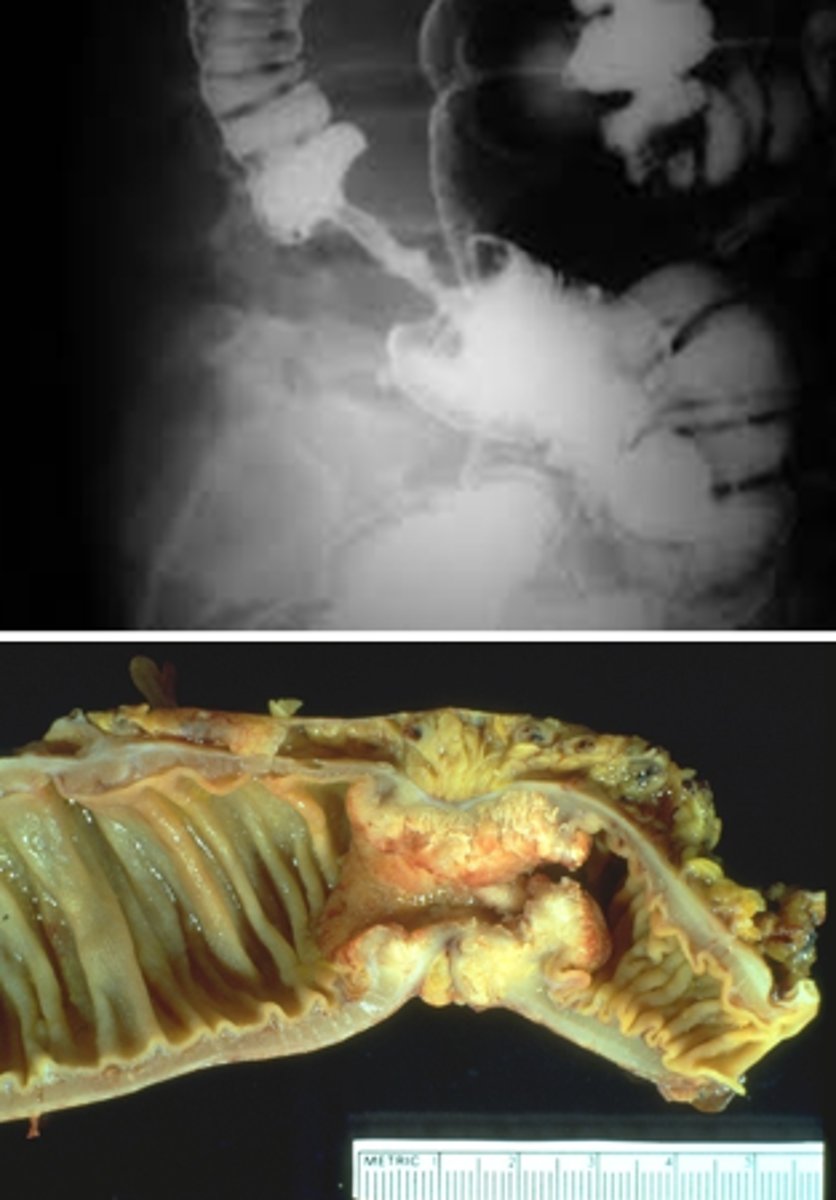

What is the gross appearence of adenomcarcinoma on the left side of the colon?

apple core lesion or napkin-ring appearnce casuesd by narrowing of the lumen

What are miscrospic/ histological findings of adeno carcinoma of the colon?

Well to poorly differentiated

marked desmoplasia

mucin producing

"dirty necrosis"